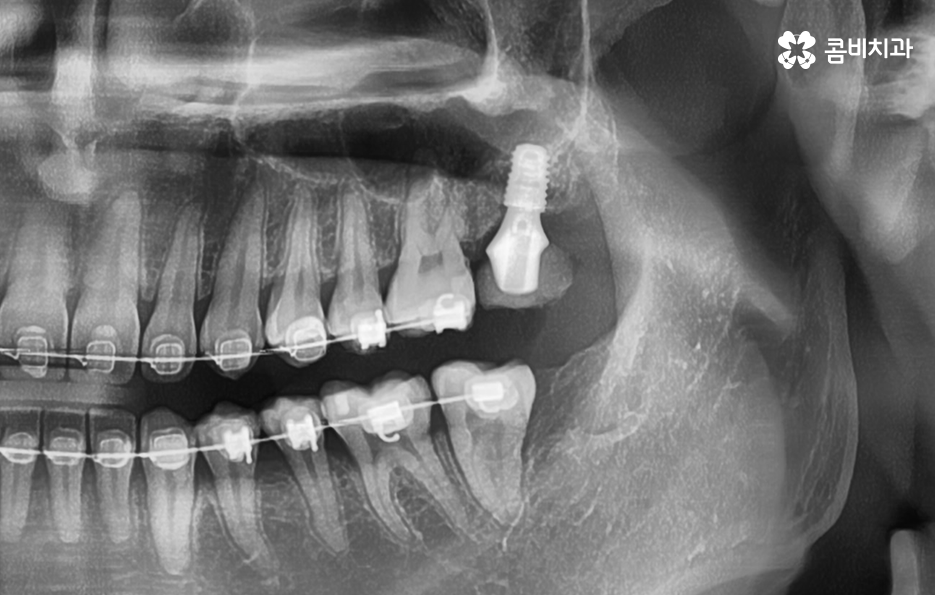

치아 상실 원인이 발생되고 발치 후 임플란트 치료 계획만 제때 잘 세우신다면 크게 무리 없이 임플란트 치료가 가능한 경우가 많은데 그 이유는 임플란트의 치료 과정에서 중요한 과정이 바로 잇몸 뼈에 임플란트의 인공치근을 식립하는 과정이기 때문이며 임플란트를 식립할 충분한 잇몸 뼈의 두께와 깊이, 골질이 확보되고 전신건강이 양호하다고 가정한다면 대부분의 임플란트 시술은 원활하게 진행될 수 있어요

치아 발치 후에는 보통 약 2,3개월 정도 잇몸과 뼈가 차오르길 기다리며 그 이후에 잇몸 상태가 임플란트를 식립하기에 충분한 상태라면 임플란트를 잇몸 뼈에 식립하고 골유착과정을 약 3개월 정도 거친 후에 지대주를 세우고 보철물을 연결하여 치료를 마무리하고 있어요. 하지만 잇몸뼈 상태가 좋거나, 뼈이식과 동시에 진행하는 경우 발치 후 바로 식립을 진행하는 경우도 있어, 정확한 치료 계획은 의사와 상의를 해보시는 게 좋아요.